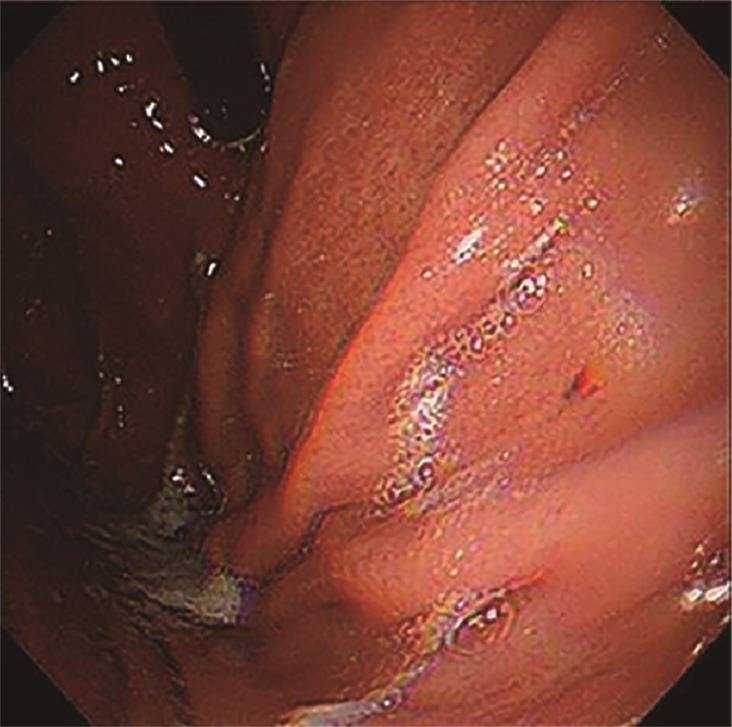

• 探讨增强CT在鉴别胆囊癌侵犯肝脏与肝癌累及胆囊病变中的应用价值

摘要:目的 探讨增强电子计算机断层扫描(computer tomography,CT)在胆囊癌侵犯肝脏与肝癌累及胆囊病变中的鉴别诊断价值。方法 收集2012年2月到2022年2月重庆医科大学附属第一医院115例患者临床及影像学资料,其中胆囊癌侵犯肝脏病例69例,肝癌累及胆囊病例46例,记录性别、年龄、肿瘤大小、肿瘤边界、胆囊形态、肝硬化、胆管扩张、肿瘤内或胆管系统内高密度影、门静脉癌栓、强化方式、强化程度、淋巴结肿大及远处转移共13个观察指标,并进行统计学分析。结果 性别(P=0.007)、年龄(P=0.002)、肿瘤大小(P=0.003)、肝硬化(P<0.001)、肿瘤内或胆管系统内高密度影(P=0.013)、门静脉癌栓(P<0.001)、强化方式(P<0.001)及淋巴结肿大(P=0.034)有统计学差异。通过回归分析筛选出年龄(敏感度为0.812,特异度为0.457)、肿瘤大小(敏感度为0.630,特异度为0.696)、门静脉癌栓(敏感度为0.326,特异度为0.957)、淋巴结肿大(敏感度为0.681,特异度为0.522)为显著分类指标,联合4个观察指标的参数绘制受试者工作特征(receiver operating characteristic,ROC)曲线,曲线下面积(area under the curve,AUC)为0.770,敏感度为0.674,特异度为0.826。结论 增强CT在鉴别胆囊癌侵犯肝脏与肝癌累及胆囊病变时,性别、年龄、肿瘤大小、肝硬化、肿瘤内或胆管系统内高密度影、门静脉癌栓、强化方式及淋巴结肿大有鉴别价值,同时结合年龄、肿瘤大小、门静脉癌栓及淋巴结肿大有助于提高鉴别诊断能力。